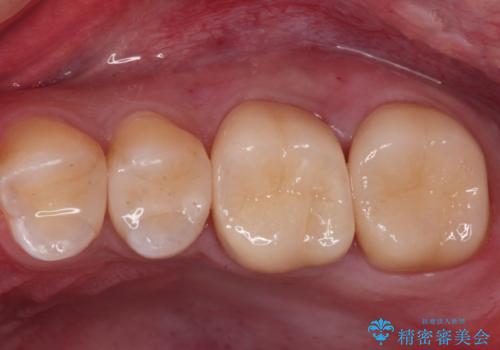

ジルコニアクラウンは表面がツルツルしていて、汚れがつきにくいです。

白い被せ物が入り、大変満足して頂きました。